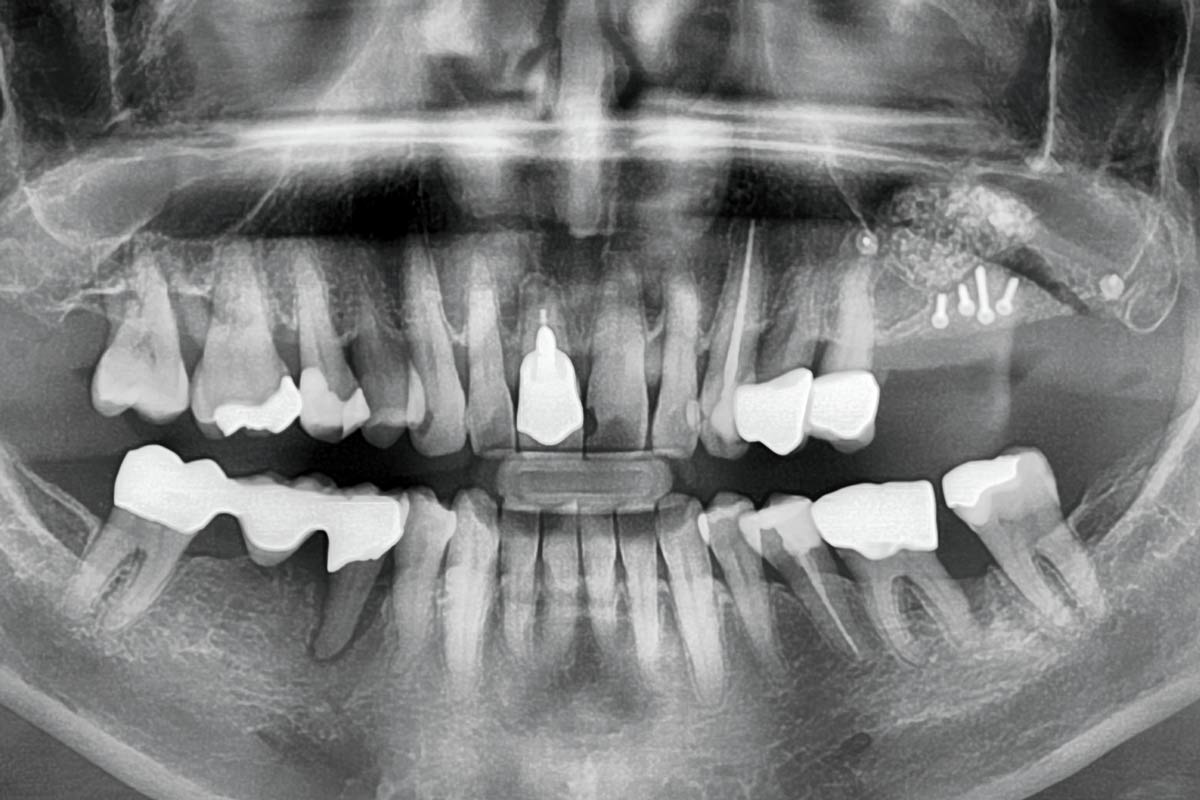

2/15 - Preoperative OPG displaying the vertical bone defectTreatment of a combined horizontal and vertical bone defect in the maxilla with maxgraft® cortico in the allogenic shell technique - Dr. R. Würdinger

3/15 - Preoperative OPG - planning of the implant placementTreatment of a combined horizontal and vertical bone defect in the maxilla with maxgraft® cortico in the allogenic shell technique - Dr. R. Würdinger